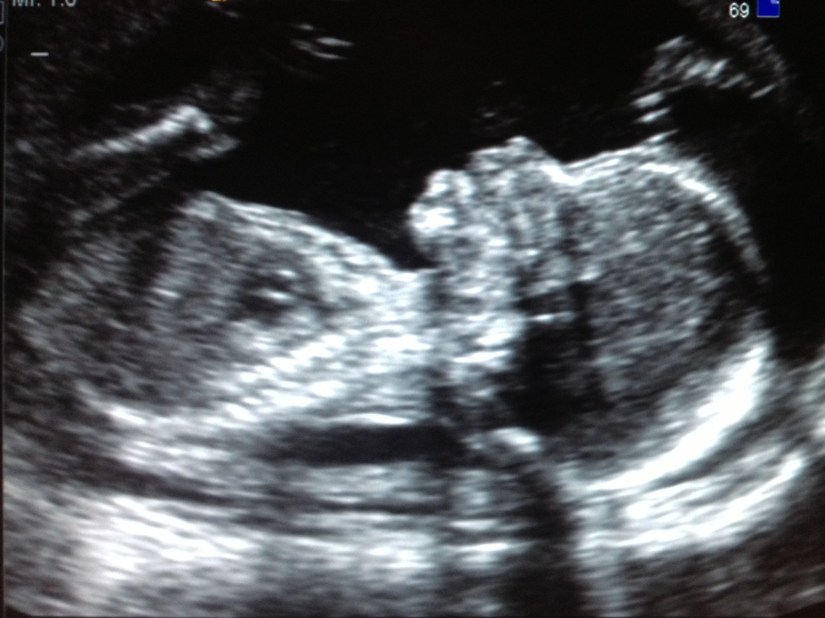

We had our anatomy scan yesterday, and everything looked great!! I was very nervous going into the ultrasound, and it didn’t help that it was in the same office where we had been sent with our last pregnancy to confirm the miscarriage. In fact, when I checked in, the receptionist looked at my chart and cheerily said to me, “Oh, looks like you were here about a year ago!” Ouch. Between the nerves and the painful reminder, it was hard to fight back tears while sitting in the waiting room. But we got called back and soon I was able to see my wiggling baby on the screen – who looked much more recognizably human than last ultrasound!

The ultrasound tech was great, and explained everything we were looking at in lots of detail. She said that baby was measuring right on track for my gestation, and that the heart, brain, stomach, kidneys, etc. all looked great. And, as you can see by the title, we are officially on team blue! I was shocked. I had this gut feeling we were having a girl, but there was no denying he is all boy! The tech was able to determine that this baby had come from my right ovary, which is of zero significance, but I thought it was interesting that she could tell. She also pointed out that I have an anterior placenta, which isn’t a concern, but explains why I haven’t been feeling much movement yet. That was comforting to know, and to see for myself that baby is definitely moving a lot, even if I’m not feeling much. He was wiggling all over the screen during the scan, kicking his legs over his head and sucking his thumb. It was very cute. My cervix was still measuring long and closed, which was a relief, as I was previously told I have a slightly elevated risk of incompetent cervix, due to a LEEP procedure I had done about 10 years ago. Thankfully, it doesn’t seem to be an issue, though I will continue to be monitored for any signs of shortening or dilation at future doctor appointments.Β  The tech also commented on how big his feet are, which was funny, since D has really big feet. D was like, “well, I guess now we know for sure it’s mine!”

Here is my sweet baby boy!

19wkus2